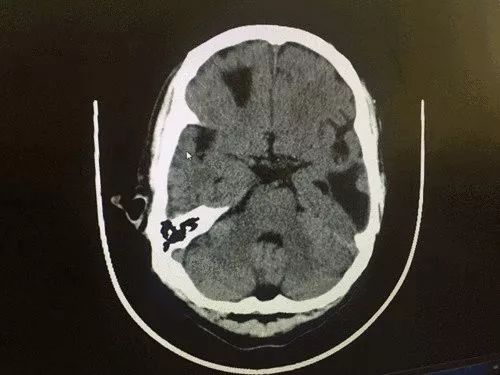

双侧放射冠区小缺血灶mra诊疗结果为双侧放射冠区多枚小缺血灶 mra提示脑动脉硬化